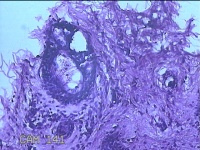

性别

男

年龄

23岁

临床诊断

右耳部肿物

一般病史

右耳前无痛性肿物20余年。

标本名称

大体所见

灰白暗红色肿物0.7x1.5x0.2cm一个,表面糜烂。

图1